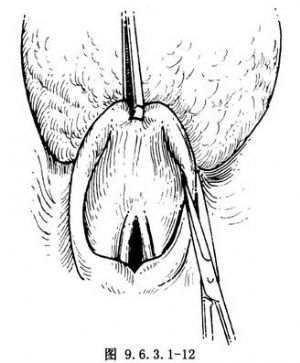

(6)切開甲舌膜進入喉咽腔:如留舌骨,在甲狀軟骨上緣水平切開甲狀舌骨膜,至兩側甲狀軟骨上角(圖9.6.3.1-11),再向上切開會厭谷黏膜,進入喉咽腔。或從舌骨上切開會厭谷黏膜進入喉咽腔。此時可見會厭尖,用Allis組織鉗抓住會厭,並向前牽拉。在會厭兩側繼續向下剪開達梨狀窩前內壁,可窺清喉內病變(圖9.6.3.1-12)。